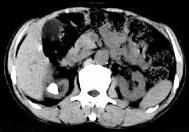

- 多项选择题男,53岁, 反复右侧腰部隐痛不适2年余,CT如图所示, 下列说法正确的是 ( )

A、右肾多发结石

B、右肾铸型结石

C、右肾钙化

D、右肾自截

E、部分肾盏有扩张积液